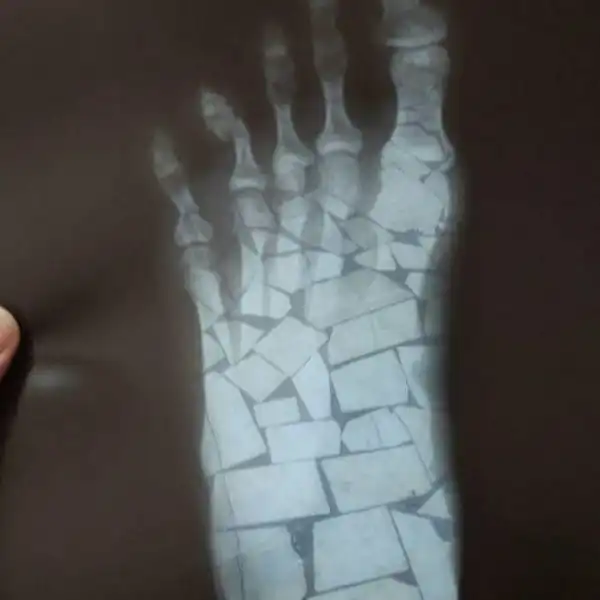

Пациент выслал фото врачу. Тот долго не мог понять, что со стопой

Просто выбирайте нормальный фон!